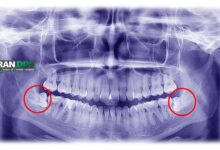

ارتودنسی یک روش جامع برای اصلاح ناهنجاریهای دندانی و فکی است. در این روش، با استفاده از براکتها و سیمها، دندانها به تدریج به موقعیت صحیح خود هدایت میشوند.